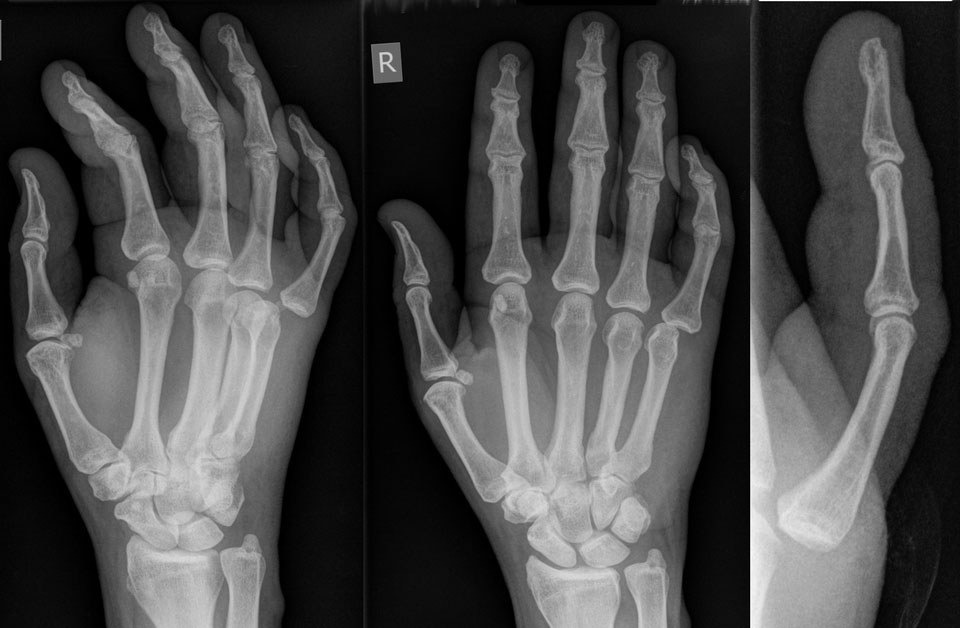

Dorsal MCP dislocations are most commonly encountered in the index and sometimes small fingers, typically from forced hyperextension of the digit on an outstretched hand. These present as obvious deformities and require imaging to assess the extent of injury or the presence of osseous injury. One key structure that helps prevent dislocation is the volar plate, a dense fibrocartilaginous component of the joint capsule located on the palmar aspect of the joint. Its primary function is to resist hyperextension. As a result, most interphalangeal dislocations occur dorsally rather than laterally or volarly. (See Figure 3.)

Figure 3. Joint Dislocation of the Metacarpophalangeal Joint |

![]() |

Source: Hellerhoff. Wikimedia commons. https://commons.wikimedia.org/wiki/File:Finger_luxation_D5_MCP.png |